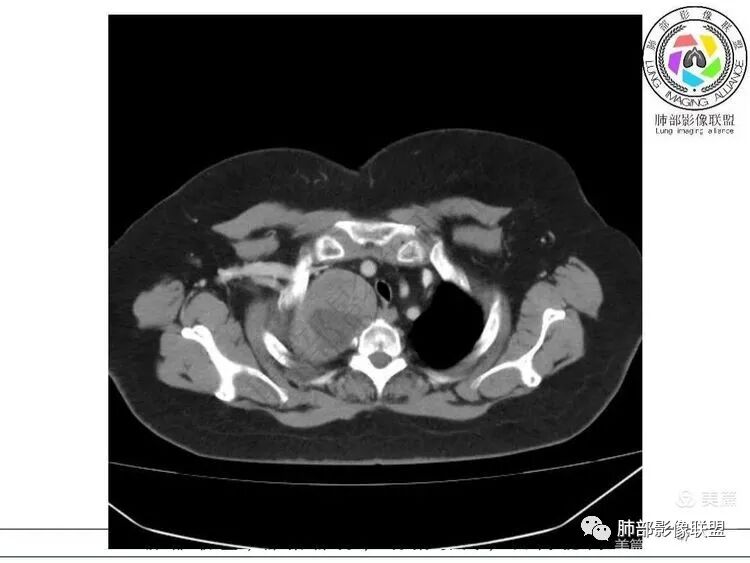

1. 右上胸廓入口区类椭圆形块影,边界清楚光整,纵向“嵌顿”于颈根部及上纵隔,向上推移右锁骨下动静脉,向外下方推移上肺胸膜及肺组织(肺血管、支气管),向前推移上腔静脉,界限清楚。

2. 块影不均匀轻度强化,可见较均匀实性区及液性密度区,未见积气、囊壁样结构、钙化或脂肪密度。可疑部分肋间动脉分支进入。

1.块影定位肺外-上纵隔。块影密度以及强化方式不支持胸腔内甲状腺肿、副节瘤、巨淋巴结增生、支气管囊肿以及畸胎瘤等。

肿块部位、密度以及强化特点聚焦于良性神经鞘瘤及孤立性纤维瘤。

2.肿块远离胸膜向上延伸不大符合胸膜来源的孤立性纤维瘤。

3.而“A/B”区密度特点以及上下径较大更支持神经鞘瘤,尽管这不属于好发部位。